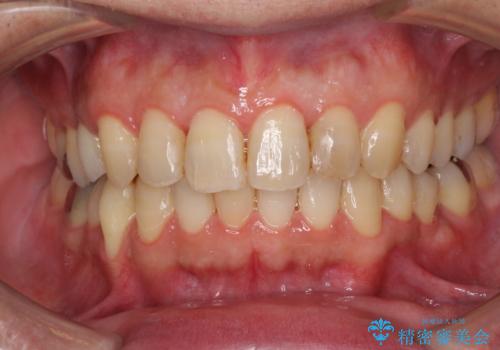

- 外に飛び出した側方の歯と、前歯のデコボコを気にして来院された患者様です。

IPR(歯と歯の間を削る)によってデコボコが解消するように設計し、インビザラインにより治療を行うこととしました。

治療途中で1年半以上通院されない時期があったため、後戻りが生じたことで治療期間が長くなってしまいました。

親知らずを抜去したことで、下顎のデコボコがきれいに解消されました。